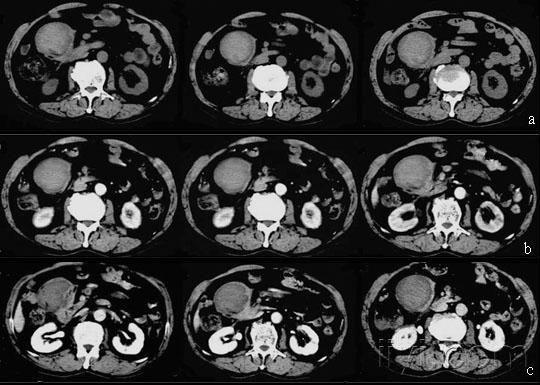

【原创】十二指肠间质瘤的ct四期通览图